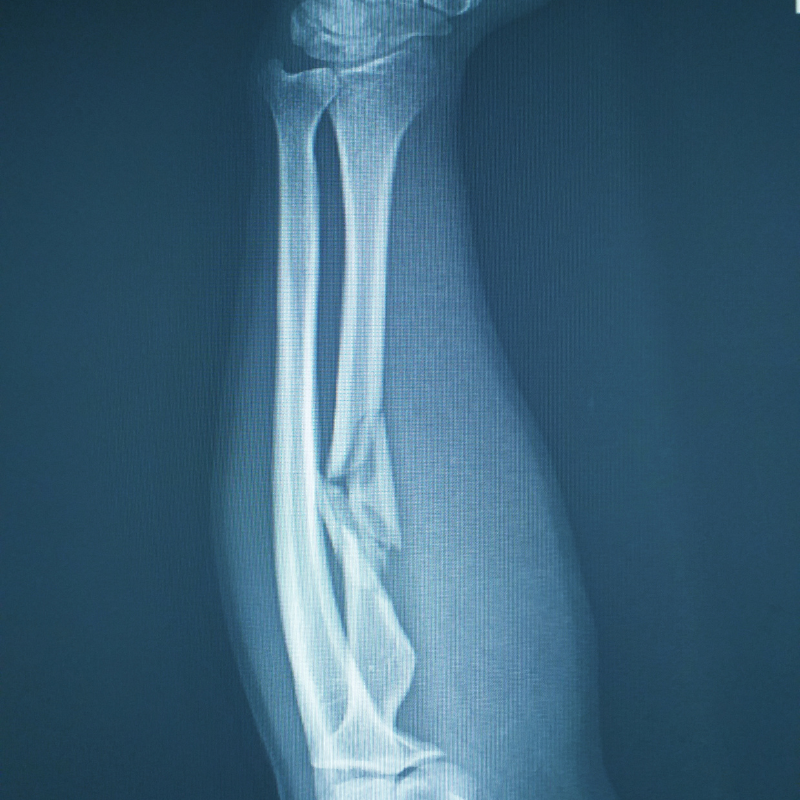

If a bone is fractured, it can sometimes cause a visible deformity in the affected area. For example, if you have a fractured arm, it may look bent or misshapen. Similarly, if you have a fractured ankle, it may appear swollen, bruised, or deformed.

If you suspect that you have a fracture, it’s important to seek medical attention right away. An x-ray is one of the most common and effective ways to diagnose a fracture accurately. At SK Radiology, we use state-of-the-art technology to provide high-quality x-ray services that can help identify fractures quickly and accurately. Our experienced radiologists will work closely with your doctor to ensure that you receive the best possible care.